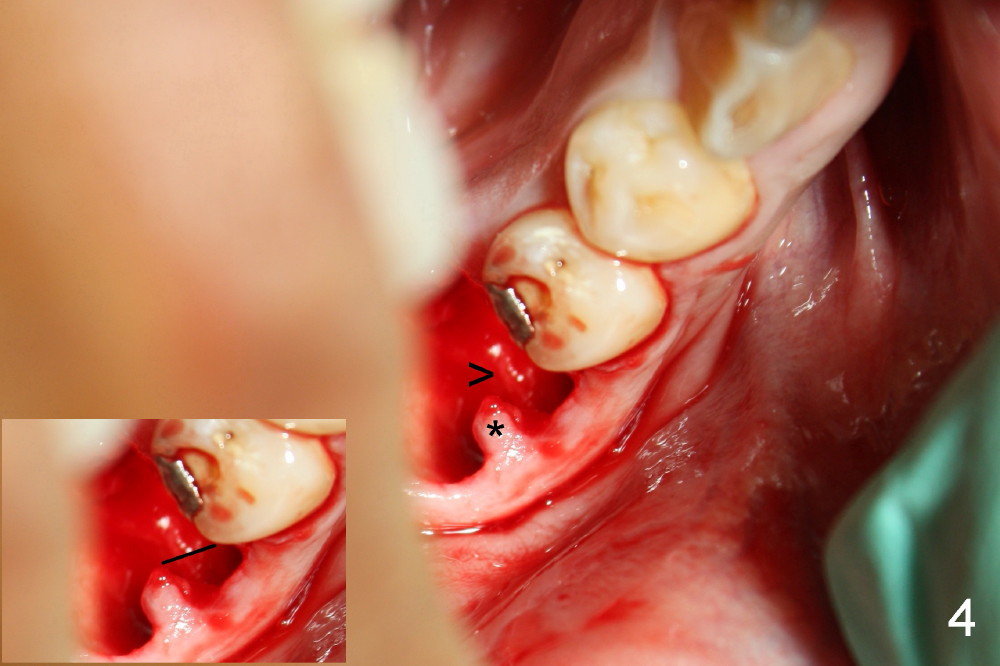

A 38-year-old lady agrees to have implant placement 7 years after loss of the crown of the lower right first molar (Fig.1,2). When the tooth is extracted, the septum is found to be low (Fig.3,4). To confirm it, a PA is taken (Fig.5). To initiate an osteotomy in the septum, it is trans-sectioned with thin osteotomes as shown in Fig.4 insert (black line). A 2 mm pilot drill is placed in the septum (Fig.6: P). The osteotomy is enlarged by 2.5-4.0 mm reamers (Fig.7,8), followed by insertion of 6x17 mm tapered tap at the depth 14 mm (Fig.9). The osteotomy is further enlarged by 4.5 and 5.0 mm reamers. A 6.0x14 mm one piece implant is placed initially. The trajectory is not ideal. A 6.0x14 mm one piece implant is placed initially. The trajectory is not ideal. The implant is removed from the osteotomy partially and reinserted with improved trajectory (Fig.11, compare to Fig.10 (red line)). Primary stability is high. There is not much bone mesiodistally so that the trajectory is easily changed in that direction. After abutment preparation, mixture of autogenous bone (harvested from reamers) and allograft is placed in the residual mesial and distal sockets (Fig.12). To contain the bone graft, an immediate provisional is placed (Fig.13 P). The occlusal plane of the provisional is significantly lower than that of the adjacent teeth to avoid micromovement of the implant. The patient is advised to eat soft food on the left side. Six days postop, the patient returns for prophy. The provisional is removed; the bone graft appears to be incorporating into the socket (Fig.14). After recementation, the provisional remains in place for 3.5 months; PA shows increased bone density in the mesial and distal sockets (Fig.15, compare to Fig.5,11). Due to insurance coverage, the patient defers fabrication of definitive restoration for at least 7 months. The immediate provisional is finally lost 8.5 months postop: the gingiva attaches to the 1-piece implant (Fig.16), while the density of the mesial socket increases (Fig.17 *) with formation of the cortex (lamina dura) coronally (v). Before the provisional (Fig.18 P) is removed for cementation of the definitive restoration, black shadow (*) is noted over the buccal gingiva. It is partially due to buccal placement (Fig.19) and partially due to buccal atrophy over a period of 10.5 months postop. How to prevent buccal placement? Positioning the first pilot drill in the septum buccolingually is a key. Eleven months post crown (Fig.20 C) cementation, the black shadow remains, but there is no tenderness. If the implant threads are immediately underneath the periosteum, there is tenderness.